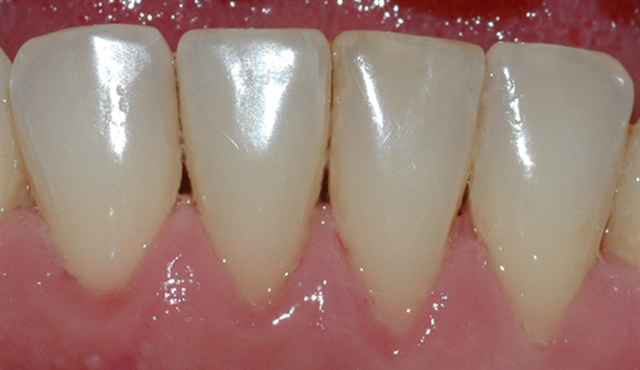

Bildet viser tilsynelatende normale tannkjøttsforhold ved tenner i underkjeven.